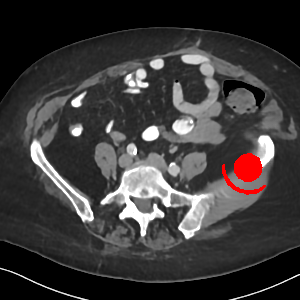

Visual comparison. As shown in Fig. 5, metallic implants such as spinal rods and hip prosthesis cause severe streaky artifacts and metal shadows, which obscure bone structures around them. cGan-CT cannot recover image intensity correctly for both cases. Sinogram domain or dual-domain methods perform much better than cGan-CT. LI, NMAR, and CNNMAR introduce strong secondary artifacts and distort the whole images. In NMAR images, there are fake bone structures around the metals, which is related to segmentation error in the prior image from strong metal artifacts. The segmentation error is also visible in NMAR sinogram. CNNMAR cannot restore the correct bone structures between rods in case 1. The tissues around the metals are over-smoothed in DuDoNet because LI sinogram and image are used as inputs, and the missing information cannot be inferred later. Our model retains more structural information than DuDoNet and generates anatomically more faithful artifact-reduced images.

Visual comparison. Fig. 7 shows two clinical CT images with metal artifacts. Case 1 is with moderate metal artifacts. cGan-CT does not suppress the artifacts completely and generates some fake details. LI, NMAR, CNN-MAR remove all the artifacts but introduce new streak artifacts, which is caused by the discontinuity in the corrected sinogram. DuDoNet outputs over-smoothed sinogram, which leads to blurred tissues close to the metal implants, such as muscle and bone. Only our model can provide realistic enhanced sinogram and remove the artifacts while retaining the structure of nearby tissues. Case 2 is very challenging as the rods bring strong metal shadows and bright artifacts around the vertebra. cGan-CT recovers the shape of vertebra but changes the overall image intensity. Other sinogram inpainting methods fail as the soft tissue and bone near the rods are heavily distorted. Our model removes part of the dark bands and reproduces correct anatomical structures around the rods.